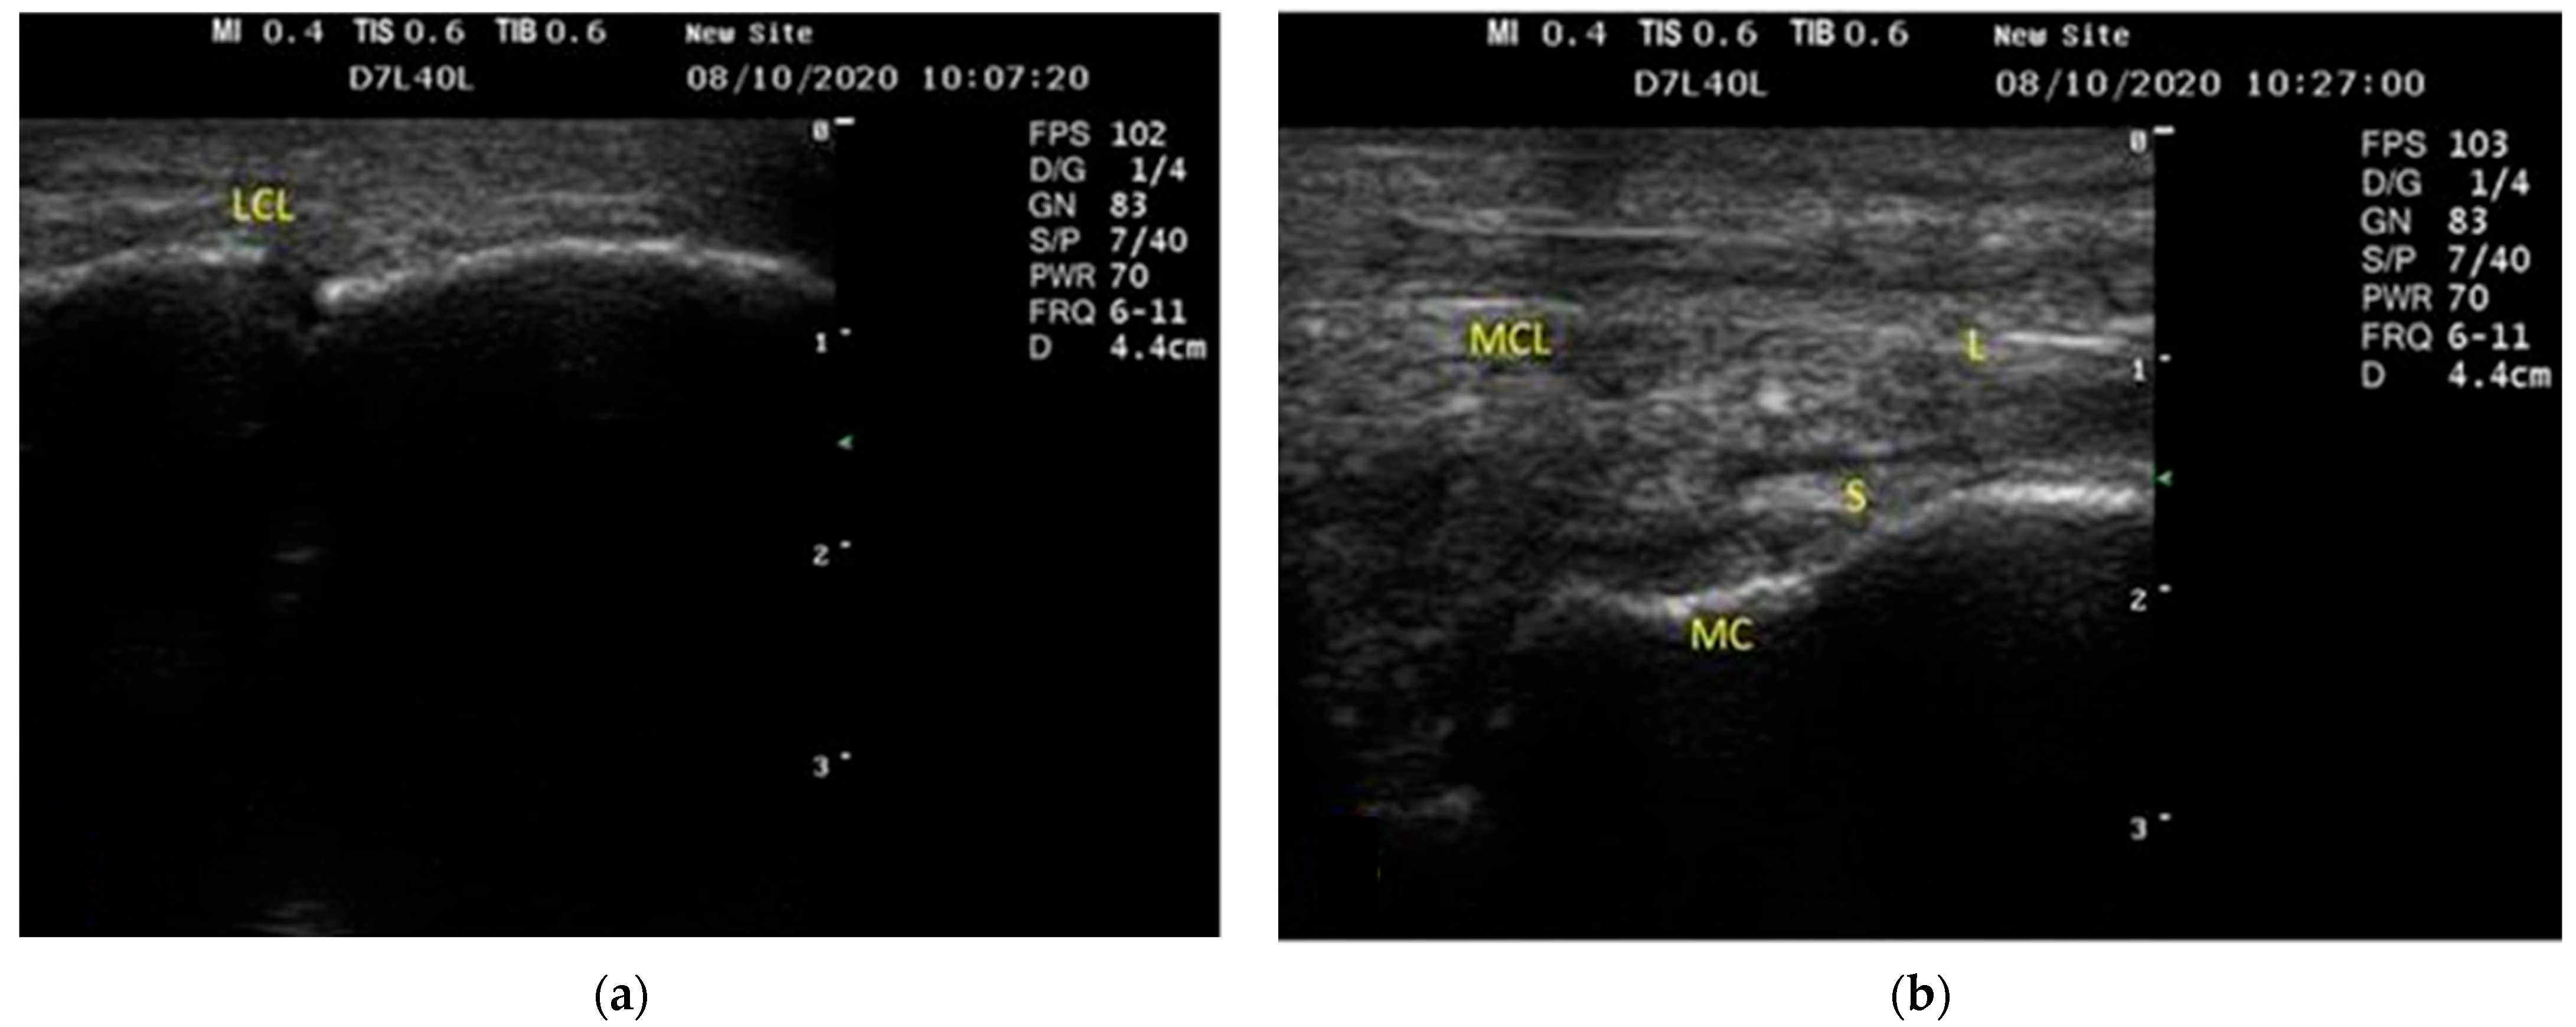

3.1. US Findings